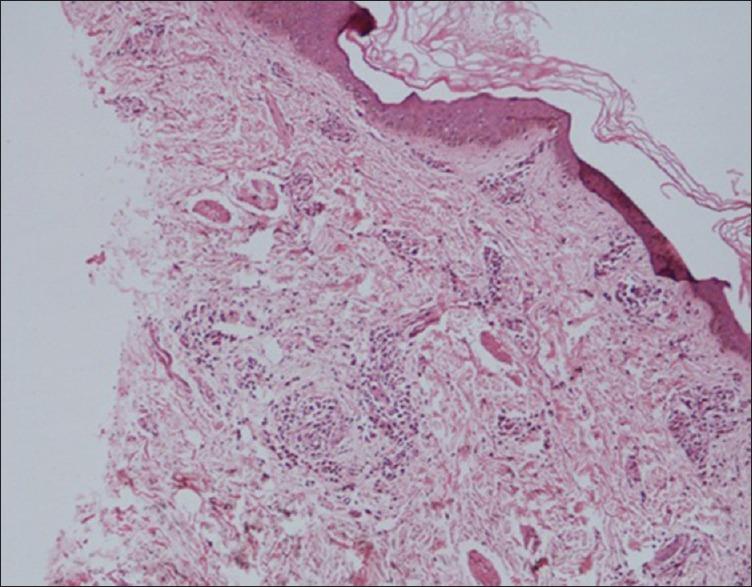

Cutaneous leucocytoclastic vasculitis and pulmonary tuberculosis: an uncommon association.